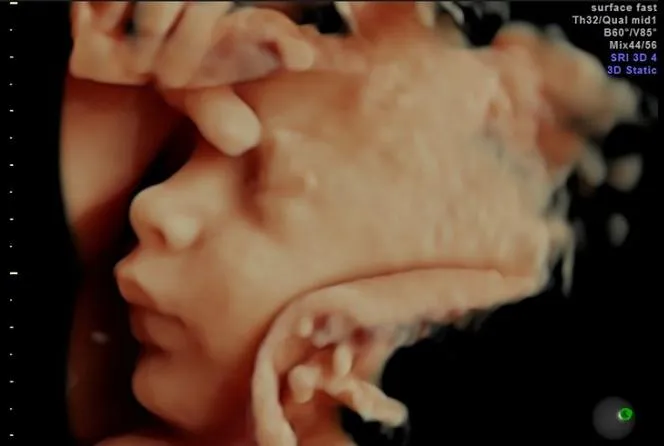

Podczas badania lekarz może zmieniać pozycję głowicy ultrasonograficznej, aby uzyskać najlepszą widoczność różnych struktur ciała płodu. W niektórych przypadkach, jeśli konieczna jest ocena długości szyjki macicy, może być wykonane dodatkowe badanie przezpochwowe. Dzięki nowoczesnym technologiom, rodzice mogą obserwować obraz swojego dziecka na monitorze w czasie rzeczywistym, co sprawia, że jest to wyjątkowe doświadczenie.

- Rodzice mogą obserwować obraz dziecka na monitorze w czasie rzeczywistym.